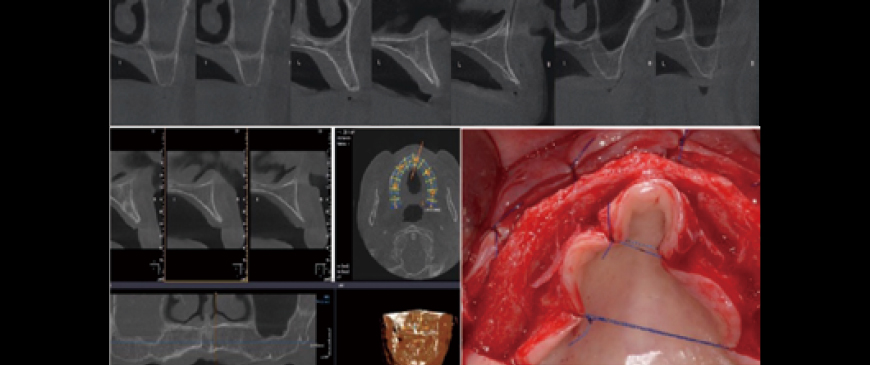

Fig 2

The 2 right premolars were extracted, and a flap raised. Identifying the mental foramen location is key for All-on-X, after which placing tilted implants at 30- 45° completes half the procedure.

Fig 3

One tilted implant was placed on each side (left and right).

Fig 4

4 straight implants were placed between the two tilted implants. Due to the very thin alveolar ridge in the anterior area, a 3.5mm ARi fixture was chosen.

Fig 5

After drilling with a 3.3mm drill, the ARi fixture provided excellent initial stability. The bone density was D2, and an ARi (2.8) 3.5x9.0(6) fixture was placed to cover the labial defect.

Fig 6

Four ARi implant fixtures were placed. A 5-6mm dehiscence occurred on the labial side, but it was limited to the machined cuff.